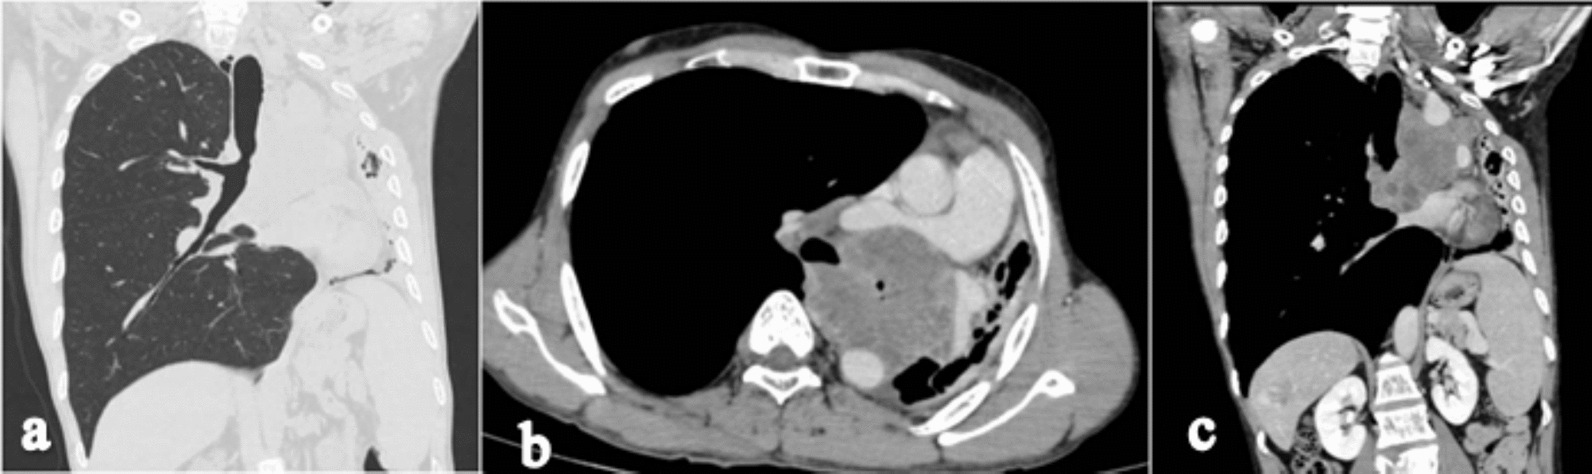

High-resolution computed tomography (HRCT) of the chest in the lung window shows cut off of the left main bronchus with a soft tissue lesion in the upper lobe of the left hemithorax (Fig. 2a). Contrast enhanced CT (CECT) of the chest axial section shows a well-defined lobulated heterogeneously enhancing mass of size 9 × 8 × 7 cm in the left upper lobe with its epicenter in the left main bronchus with complete occlusion of the left main bronchus (Fig. 2b). CECT chest coronal section shows a complete collapse of the left upper lobe with an ipsilateral shift of mediastinum and compensatory hyperinflation of the right lung with minimal left-sided pleural effusion (Fig. 2c). There was no mediastinal lymphadenopathy. CECT axial section shows complete encasement of the aortic arch (Fig. 3a), 150° encasement of the right pulmonary artery with its narrowing (Fig. 3b), and sagittal section shows > 180° encasement of the descending aorta (Fig. 3c).

Fig. 2.

High-resolution computed tomography chest coronal section (a) shows cut off of the left main bronchus, loss of left lung volume with hyperinflation of the right lung, and herniation across the midline. Contrast enhanced computed tomography chest axial section (b) shows a well-defined lobulated heterogeneously enhancing mass in the left upper lobe with its epicenter in the left main bronchus with complete occlusion of the left main bronchus. Contrast enhanced computed tomography chest coronal section (c) shows a complete collapse of the left upper lobe with a shift of mediastinum and compensatory hyperinflation of the right lung with minimal left pleural effusion